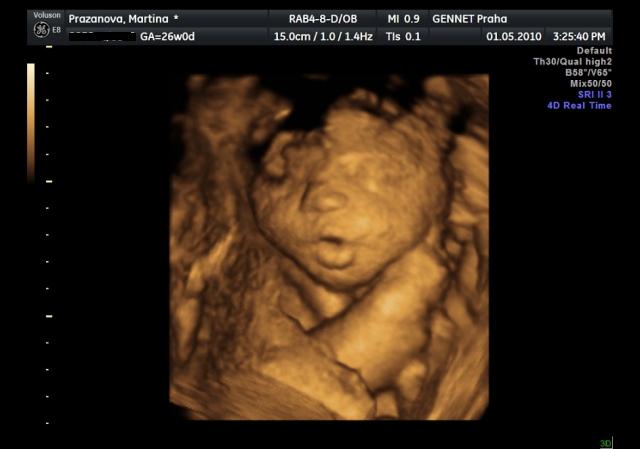

Už se nemůžeme dočkat 1.5....jdeme na 4D UTZ, tak doufám, že se nám ten náš klučík ukáže v plné své kráse 🙂))